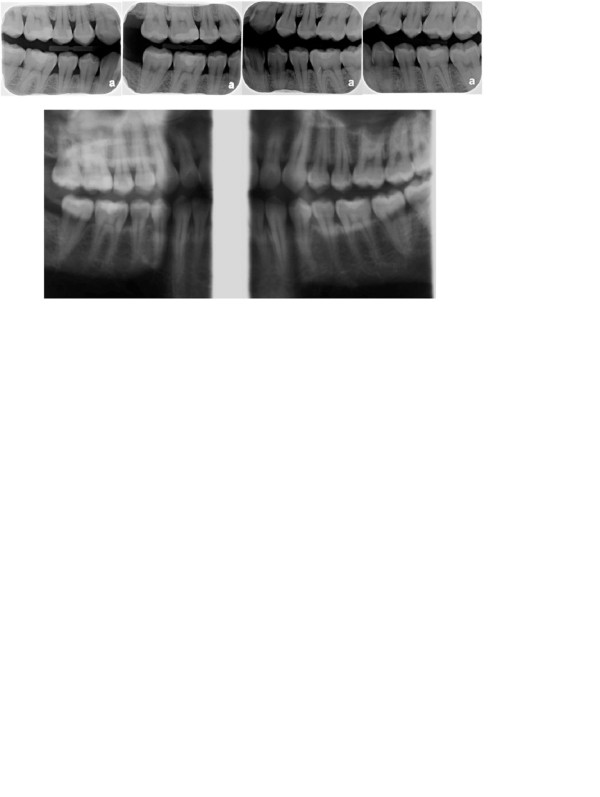

Chụp X quang răng cánh cắn (Bite wing)

Chụp X quang cánh cắn (hay còn gọi là bitewing) là một dạng hình ảnh giúp kiểm tra cấu trúc của răng hàm trên và dưới, đặc biệt phù hợp để phát hiện sâu răng giữa các răng và tình trạng tiêu xương quanh răng. Là công cụ hiệu quả trong dự phòng, giúp hạn chế các vấn đề răng miệng nặng hơn về sau.

Chi phí chụp X quang cánh cắn thường thấp hơn, chỉ từ 100.000 – 250.000 đồng/bộ, tùy từng cơ sở. Bên cạnh đó, hình ảnh bitewing còn giúp theo dõi quá trình điều trị sâu răng, chỉnh nha hay các bệnh lý khác liên quan đến cấu trúc răng. Đây là loại hình phổ biến, phù hợp với nhiều đối tượng và được khuyến khích thực hiện định kỳ để duy trì sức khỏe răng miệng tốt nhất.